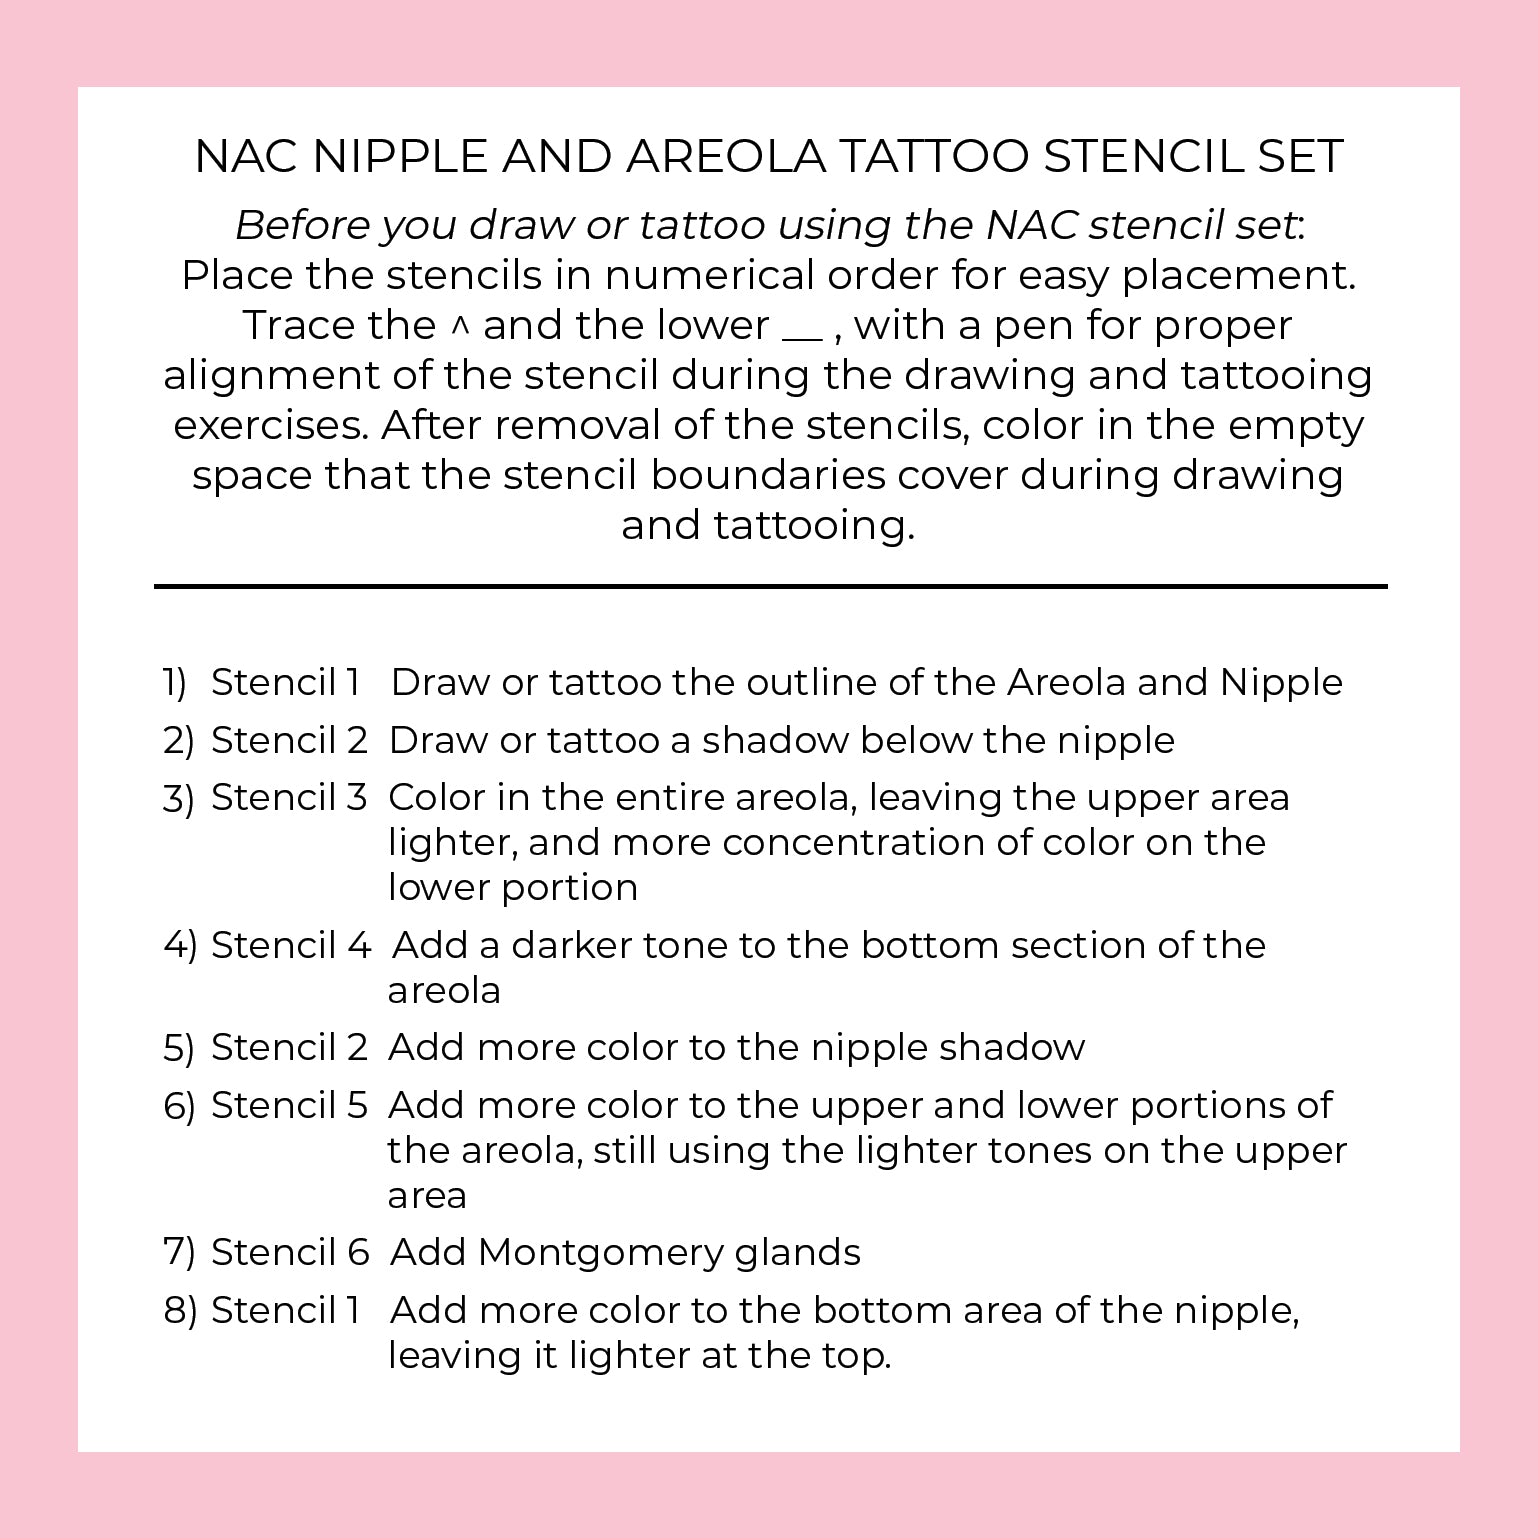

Creating a realistic, 3-D nipple/areola tattoo can be challenging — especially for new technicians learning the process. This 3-D Areola Tattoo Stencil Set is designed to simplify and guide you through each stage of areola restoration. With 6 professional-grade stencils and an 8-step workflow, you’ll have a clear visual roadmap while leaving space for your artistic interpretation and shading techniques to shine.

Made from 10mil polycarbonate film, these stencils are impact-resistant, clear, and durable — safe for practice pad work and even direct use during live procedures. They are steam autoclavable, alcohol-safe, and compatible with Sani-Cloth wipes, making them easy to clean and reuse safely. Ideal for PMU artists, medical tattooists, and professionals offering breast reconstruction finishing, scar camouflage, or restorative areola tattooing.